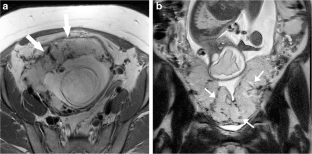

Fig. 1

Fig. 2

Fig. 3

Fig. 4

Fig. 5

Fig. 6

Fig. 7

Fig. 8

Fig. 9

Fig. 10

Fig. 11

Fig. 12